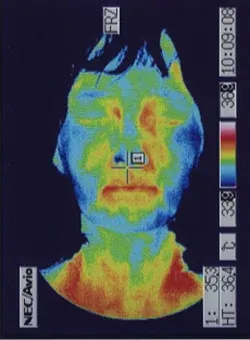

突発性難聴の治療で高圧酸素室に入って治療をした時、耳ぬきがうまくいかずに滲出性中耳炎になってしまいました。痛みは無いので鼓膜に穴をあけるのもとても不安です。滲出性中耳炎は、鍼治療でよくなりますか?

内耳のリンパの流れを良くすることで改善することが多いです。

滲出性中耳炎は、痛みが無いので癖になってしまうことが多いのですが、比較的、鍼治療が効果的です。お医者様は、鼓膜にチューブを入れることがあるのですが、鼓膜の中に落ち込んでしまうこともあるので、鍼治療をされる方も多いです。不安や恐怖が多いほど、症状が改善しなくなることが多いので、ストレスをためないようにしましょう。

詳しくは、 滲出性中耳炎の鍼治療 をご覧ください。